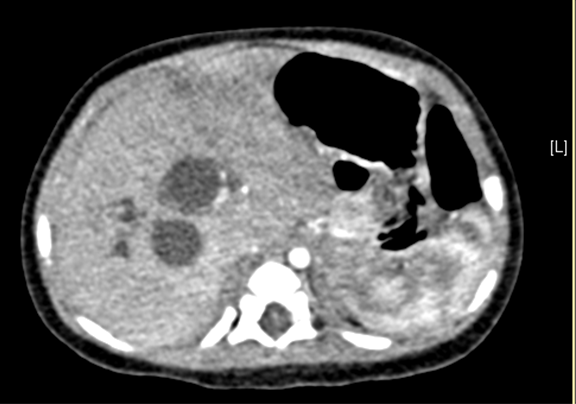

术前CT检查:

静脉期

上腹部增强CT:先天性胆管扩张症(胆总管囊肿)可能性大。

将0.625mm双源薄层CT资料的静脉期和动脉期Dicom格式文件导入海信CAS系统。

通过调节窗宽窗位调整CT序号,对肝实质,胆囊,下腔静脉,肿瘤,肝动脉、门静脉及肝静脉等进行三维重建;系统自动计算肝脏体积。